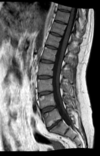

Fratura compressiva da coluna lombar

Causa achatamento do corpo e acunhamento geralmente anterior.

Tipo mais comum de fratura da coluna lombar

Estável.

Mecanismo flexão anterior ou lateral